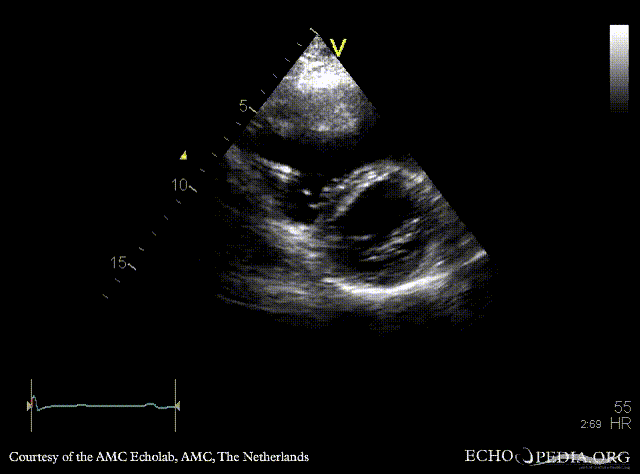

ARVD

PLAX: right ventricle dilatation in patient with ARVD PSAX: dilated right ventricle